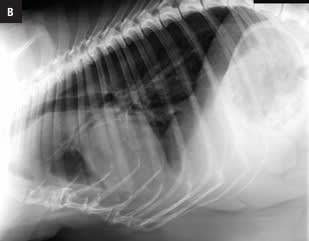

Este atlas de consulta rápida ayudará al clí­nico a obtener la máxima información de sus estudios radiográficos del tórax. Presenta gran cantidad de imágenes que guiarán al veterinario en su interpretación radiográfica, desde la misma técnica, la posición más idónea según la patologí­a que se sospeche o el estado clí­nico del paciente, o variaciones fisiológicas, hasta el órgano o estructuras torácicas a evaluar. Presenta montajes anatómico-radiográficos para ayudar a visualizar las estructuras que se están valorando en la radiografí­a. Aporta imágenes de las proyecciones radiográficas torácicas normales de más de 30 razas caninas para su comparación directa lo que hacen de este libro una guí­a de referencia de radiografí­as torácicas raciales.

Capítulo 1. Introducción. Capítulo 2. Indicaciones. Capítulo 3. Obtener la imagen radiográfica torácica. Técnica. Proyecciones. Capítulo 4. Factores fisiológicos que  pueden influir en la imagen radiográfica. Edad. Sexo. Condición corporal. Fase respiratoria. Ciclo cardíaco. Capítulo 5. La raza. Capítulo 6. Interpretación de la imagen  radiográfica. Límites torácicos. Vértebras. Esternón. Arco costal. Diafragma. Aparato respiratorio. Tráquea. Bronquios. Pulmones. Sistema cardiovascular. Corazón. Grandes  vasos. Vasos lobares. Mediastino. Esófago. Linfonódulos. Pleura. Capítulo 7. Radiografía torácica por razas caninas. American Staffordshire. Basset hound. Beagle. Boxer.  Bulldog Francés. Bull Terrier. Caniche Toy. Carlino. Cavalier King Charles Spaniel. Chihuahua. Cocker Spaniel. Dálmata. Doberman. Golden Retriever. Gran Danés. Husky Siberiano.  Labrador Retriever. Maltés. Mastín Español. Pastor Alemán. Pequeño Lebrel Italiano. Pinscher Miniatura. Pointer. Schnauzer Miniatura. Setter Irlandés. Shih Tzu. Teckel. Terranova.  Welsh Corgi Pembroke. West Highland White Terrier. 9Yorkshire Terrier. Índice analítico